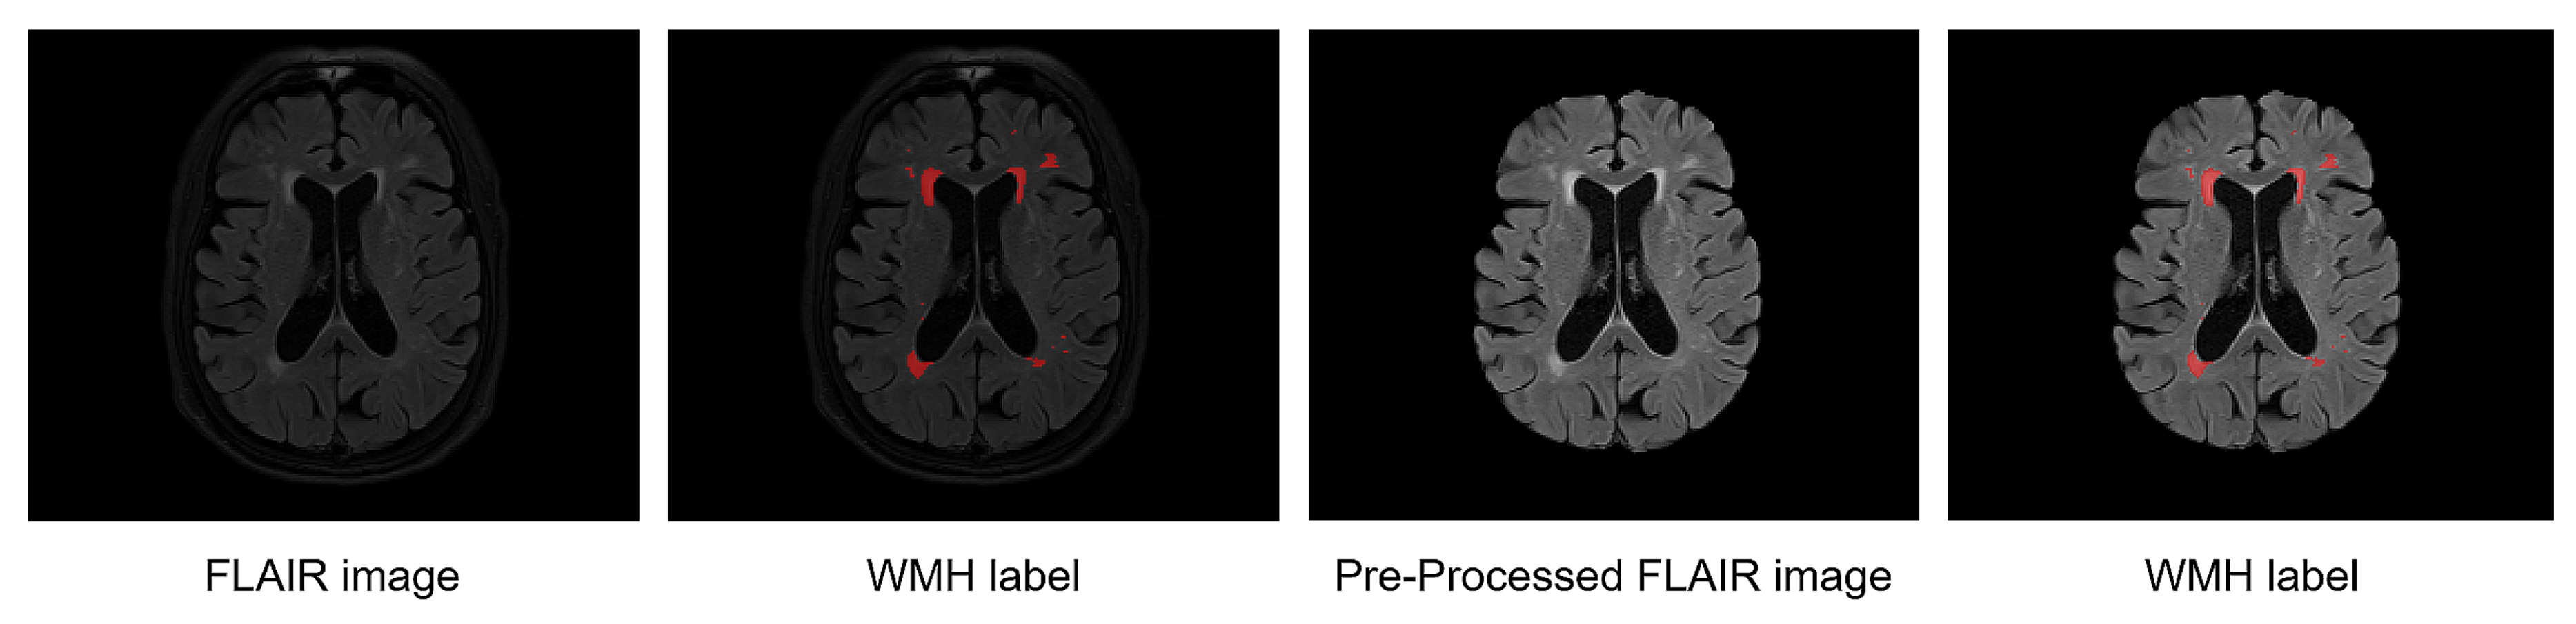

2.5. WMH Segmentation: Supervised Learning-Based Segmentation

2.5.1. Annotated Labeling with Radiologists

2.5.2. Preprocessing